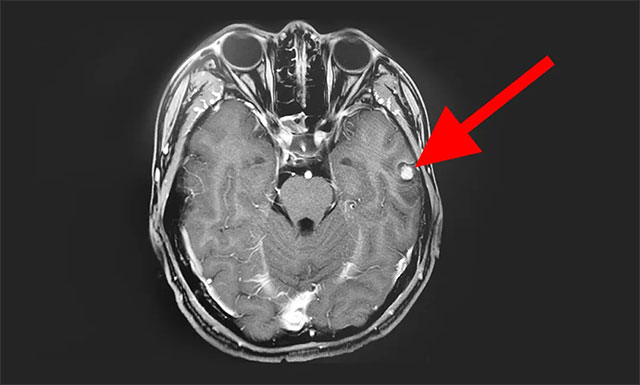

入院后,完善其各項(xiàng)檢查,為了更好的手術(shù),并進(jìn)一步確定病灶位置,增強(qiáng)掃描,進(jìn)行了頭部MRI平掃+增強(qiáng)+MRS+MRSI,影像結(jié)果顯示:患者左側(cè)顳葉可見一團(tuán)塊狀異常信號(hào), T1WI 低信號(hào)為主,其內(nèi)見結(jié)節(jié)狀高信號(hào),T2WI高信號(hào)為主,邊緣低信號(hào),F(xiàn)LAIR與DWI低信號(hào)為主、低混雜信號(hào);MRS示體素位于左側(cè)顳葉病灶,波譜基線不穩(wěn)。

▲ 患者病灶位于左側(cè)顳葉,其波譜圖顯示異常